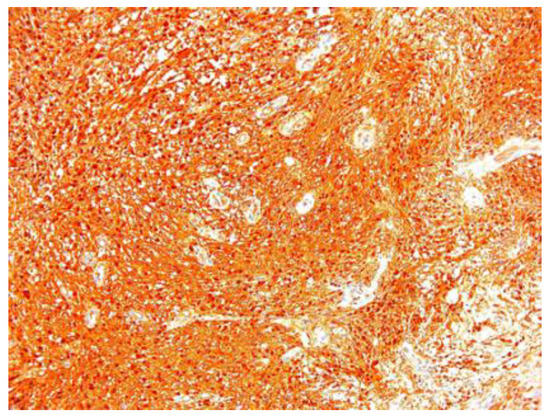

| 2 | 53 | F | enucleation | 7.5/5.5/4.5 | S100+, CD34+, SMA− |

| 5 | 48 | F | enucleation | 2.4/1.8/1.5 | S100+, collagen IV+, SMA− |

| 6 | 36 | F | enucleation | 0.7/0.4/0.4 | S100+ |

| 7 | 52 | F | enucleation | 3/2.7/2.5 | S100+, collagen IV+, SMA− |

| 8 | 77 | M | enucleation | 4.1/3.2/2.7 | S100+, SMA− |

| 9 | 72 | F | enucleation | 1.4/1.1/0.9 | S100+ |

| 10 | 57 | F | enucleation | 3.1/2.8/2.6 | S100+, SMA−, |

| 12 | 56 | F | enucleation | 2.2/2.1/1.3 | S100+, collagen IV+, CD34+, SMA− |

| 14 | 75 | F | enucleation | 2.1/1.1/1.5 | S100+ |

| 15 | 31 | F | enucleation | 3.2/1.9/1.8 | S100+, SMA− |

| 16 | 62 | F | enucleation | 3.1/1.8/1.4 | S100+, CD34+, collagen IV+, SMA− |